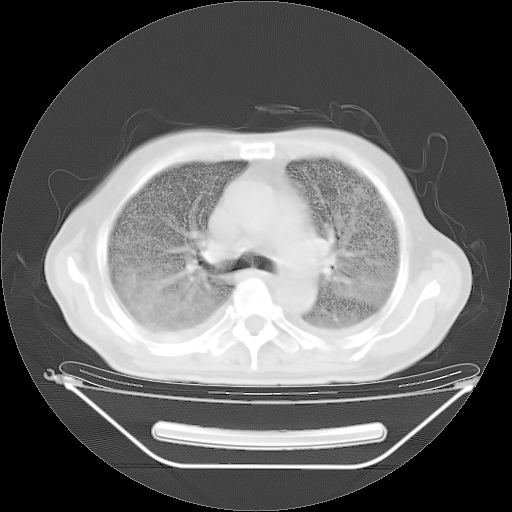

今天复查肺部CT,发现双肺广泛磨玻璃样改变。所以我把3月19日和5月9日相隔50天的肺部CT上传。请大家会诊。

2009年3月19日肺部CT片。

2009年3月19日肺部CT

大致读了系列胸部CT:纵隔窗无明显异常,肺窗:从4、27至今:主要是双肺中下野外带可见毛玻璃样改变,目前处于急性肺泡炎阶段,至于原因考虑1、结替组织或胶原血管性疾病所致?2、恶性疾病如恶组在肺部所致的表现或细支气管肺泡癌?3、药物或其它原因如肺蛋白沉着症所致肺泡炎目前不太可能?总之,明天就去请我院的呼吸科、感染科、血液科和临免专家会诊哈。